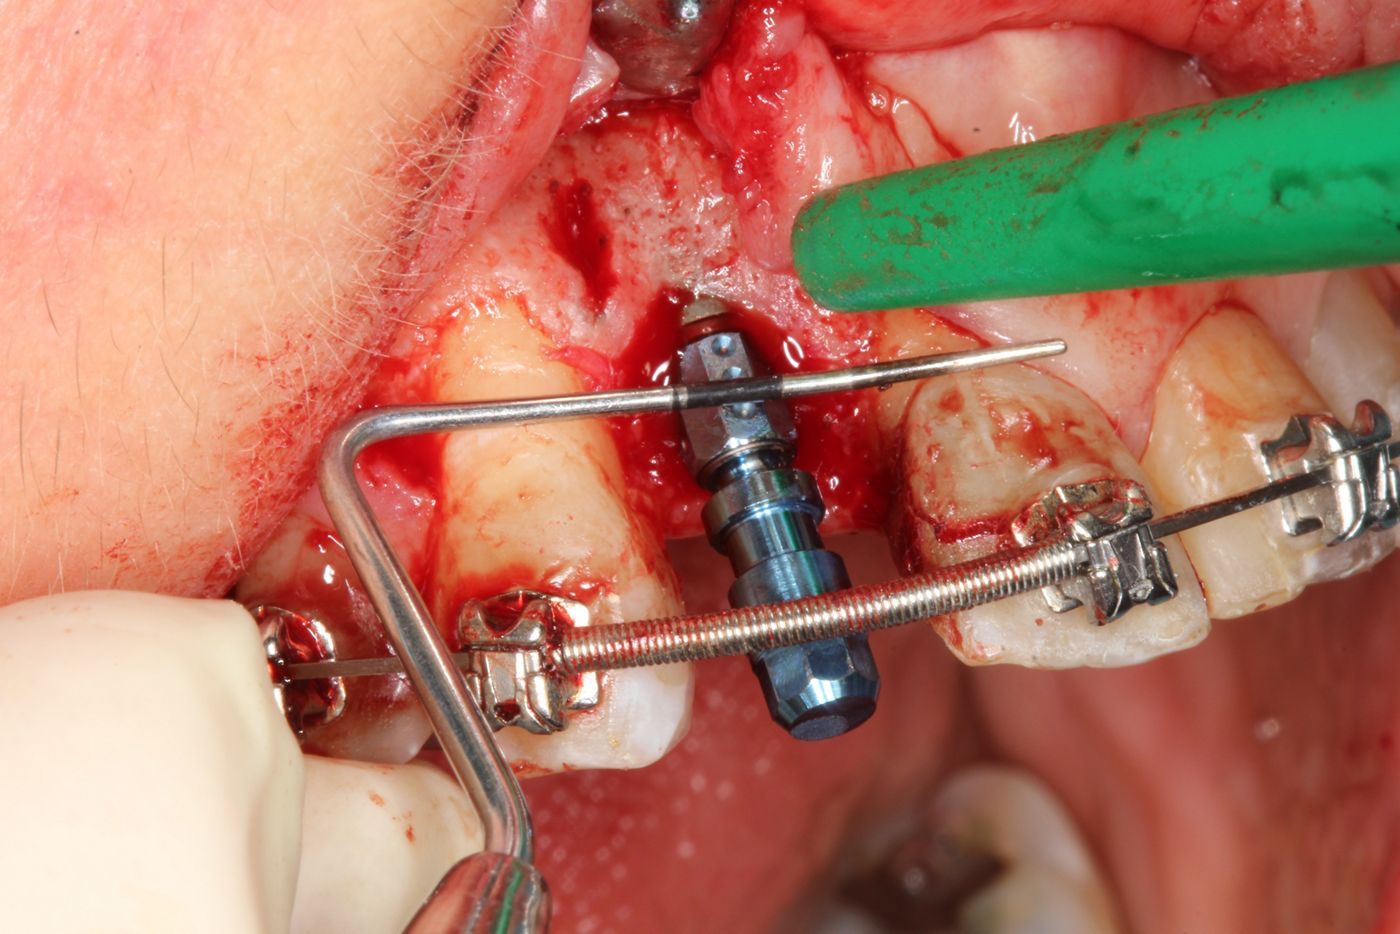

Surgical procedure

To reduce scar formation a marginal incision was made from #13 to #11, with a distal releasing incision at #13 (Figs. 4,5). The flap was deflected at the exposed bone – a narrow ridge in all dimensions (Figs. 6,7). After the pilot drilling and x-ray control of the axis (Figs. 7-9), the preparation of the implant bed was continued with the 2.2mm drill and the profile drill (Figs. 10-13). Next, the 2.9mm Straumann® BLT implant (Roxolid®, SLActive®) was inserted with a primary stability of 25Ncm, and the anatomical healing abutment was then connected (Figs. 14-18). Due to the limited bone thickness in the buccal region and a small coronal dehiscence, bone augmentation with botiss cerabone® and a Jason® membrane was also performed (Figs. 19-23). The flap was closed passively with 5-0 Prolene sutures (Figs. 24-27). The patient was prescribed antibiotics, analgesia and anti-inflammatory medication, as well as chlorhexidine rinse for 1 week. Suture removal and subsequent healing was uneventful.